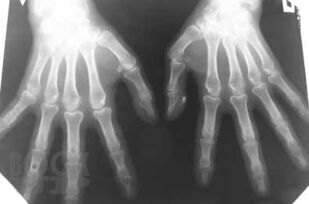

В основу издания положено собрание избранных клинических разборов, регулярно проводимых в ЦНИИ гастроэнтерологии. Многие из приведенных наблюдений являются уникальными, представляя собой либо клинический раритет, либо описание необычного течения давно известного заболевания, либо недавно описанное новое заболевание, прижизненный диагноз которого стал возможным благодаря внедрению новейших диагностических технологий. Особое внимание уделено и уникальным коррекционным вмешательствам.